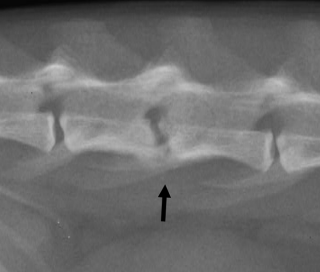

일반적으로 discospondylitis의 전형적인 방사선 사진은

이런식으로 골융해 양상이 일반적인데 반해